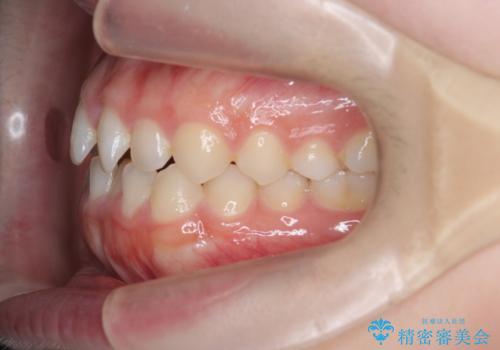

前歯のガタつき・ねじれを治すマウスピース矯正

- 前歯のねじれ、ガタつきを改善し綺麗な歯並びにしたいと希望され来院されました。

マウスピース矯正インビザラインによる矯正治療を計画しますが、マウスピース矯正で治りにくい歯のねじれを事前にワイヤー矯正でしっかりとなおしておくことで矯正治療期間の短縮できるような治療計画を立てます。

マウスピース矯正を始める前にワイヤー部分矯正を行ったことで改善のしにくい歯のねじれをしっかりと治すことができました。